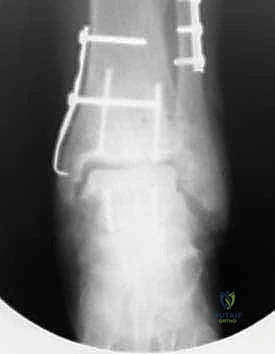

- في بعض الحالات المعقدة، قد يتطلب الأمر إجراء قص عظمي في الكعب (Malleolar Osteotomy) لفتح المفصل بالكامل ورؤية السطح المتضرر بوضوح، ثم يتم إعادة تثبيت هذا العظم لاحقاً.

- لضمان الثبات التام، يتم تثبيت الطعم باستخدام براغي دقيقة جداً (غالباً تكون قابلة للامتصاص البيولوجي أو براغي تيتانيوم غاطسة تحت مستوى الغضروف حتى لا تحتك بالمفصل).

صور إضافية من داخل غرفة العمليات والخطوات الجراحية

ندرك أهمية توثيق الخطوات الجراحية لطلاب الطب والمرضى الراغبين في فهم دقة الإجراء. هذه الصور توضح مراحل زراعة وتثبيت الطعم العظمي الغضروفي بدقة متناهية تحت إشراف أ.د. محمد هطيف.